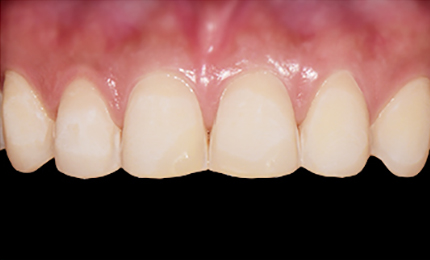

시술 후

• 시술전

최소삭제 0.1mm - 0.2mm, 최대 0.3mm